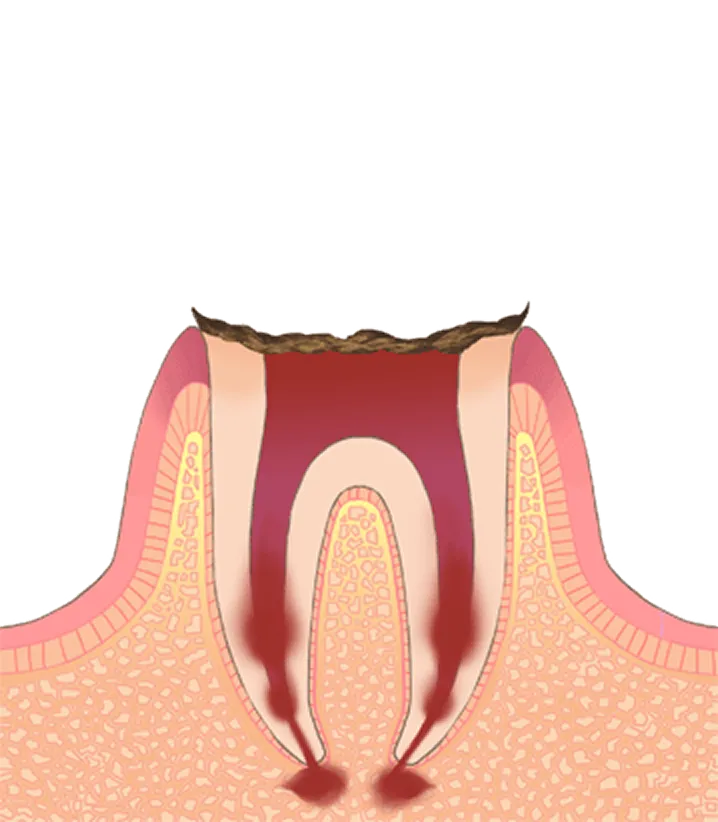

虫歯の進行と症状

- Q虫歯を放置するとどうなりますか?

- A虫歯は自然に治ることはありません。放置すると徐々に進行し、神経に達して強い痛みが生じます。最終的には歯を失う原因となり、周囲の歯にも悪影響を及ぼします。早めの受診が歯を守る最善の方法です。